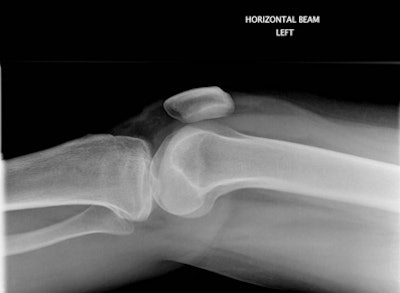

Figure 1A: False-negative outcome after a knee radiograph. The patient within the standard delayed reporting arm was discharged by the accident and emergency (A&E) clinician as normal for further A&E review if required. All images courtesy of Maryann Hardy, PhD.

Figure 1B: Tibial plateau fracture with visible lipohemarthrosis was identified on image review. The patient was recalled to A&E for orthopedic intervention several days later.Part of a randomized controlled trial, the study, which began in 2009, focused on musculoskeletal (MSK) patients who underwent radiographic imaging and were then divided into two reporting arms, standardized (delayed) and immediate. A total of 1,502 patients from five hospitals within three National Health Service (NHS) Trusts (or groups of hospitals) across the north of England were included in the final study analyses. Of these, 752 patients, accounting for 839 examinations, were recruited to the immediate reporting arm and 750 patients (849 examinations) were recruited to the delayed reporting arm, with follow-up conducted by means of a questionnaire at eight weeks postattendance date for the evaluation of short-term injury recovery status.